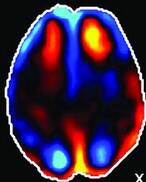

Een doorbloedingsscan, Pet-scan (Positron Emission Tomography)

of SPECT scan (Single Photon Emission Computed Tomography) toont het functioneren aan, of er bijvoorbeeld een doorbloedingsstoornis of verhoogde activiteit is. Het spoort dus veranderingen in bloedstroom en metabolisme in hersenen. Hiermee is diffuus letsel vaker wel zichtbaar te maken maar ook niet altijd.

• De Pet scan maakt gebruik van kleine hoeveelheden radioactieve materialen, radiotracers genaamd, een speciale camera en een computer om de orgaan- en weefselfuncties te beoordelen. Door lichaamsveranderingen op cellulair (neuraal) niveau te identificeren, kan de PET-scan afwijkingen of een ziekte detecteren voordat het duidelijk wordt in andere beeldvormingstests. Het meet niet alleen doorbloeding, maar ook de suikerhuishouding (glucosemetabolisme) en zuurstofopname. De ingespoten radioactieve stof verdwijnt snel uit het lichaam en is niet schadelijk. Diffuus letsel is soms beter in beeld te brengen dan bij een MRI-scan. Als er twijfels zijn over een diagnose, zou deze scan soms het antwoord kunnen geven. Echter het inzetten van deze techniek vereist een urgente medische situatie. Niet om bewijslast te leveren over langer geleden opgelopen letsels.